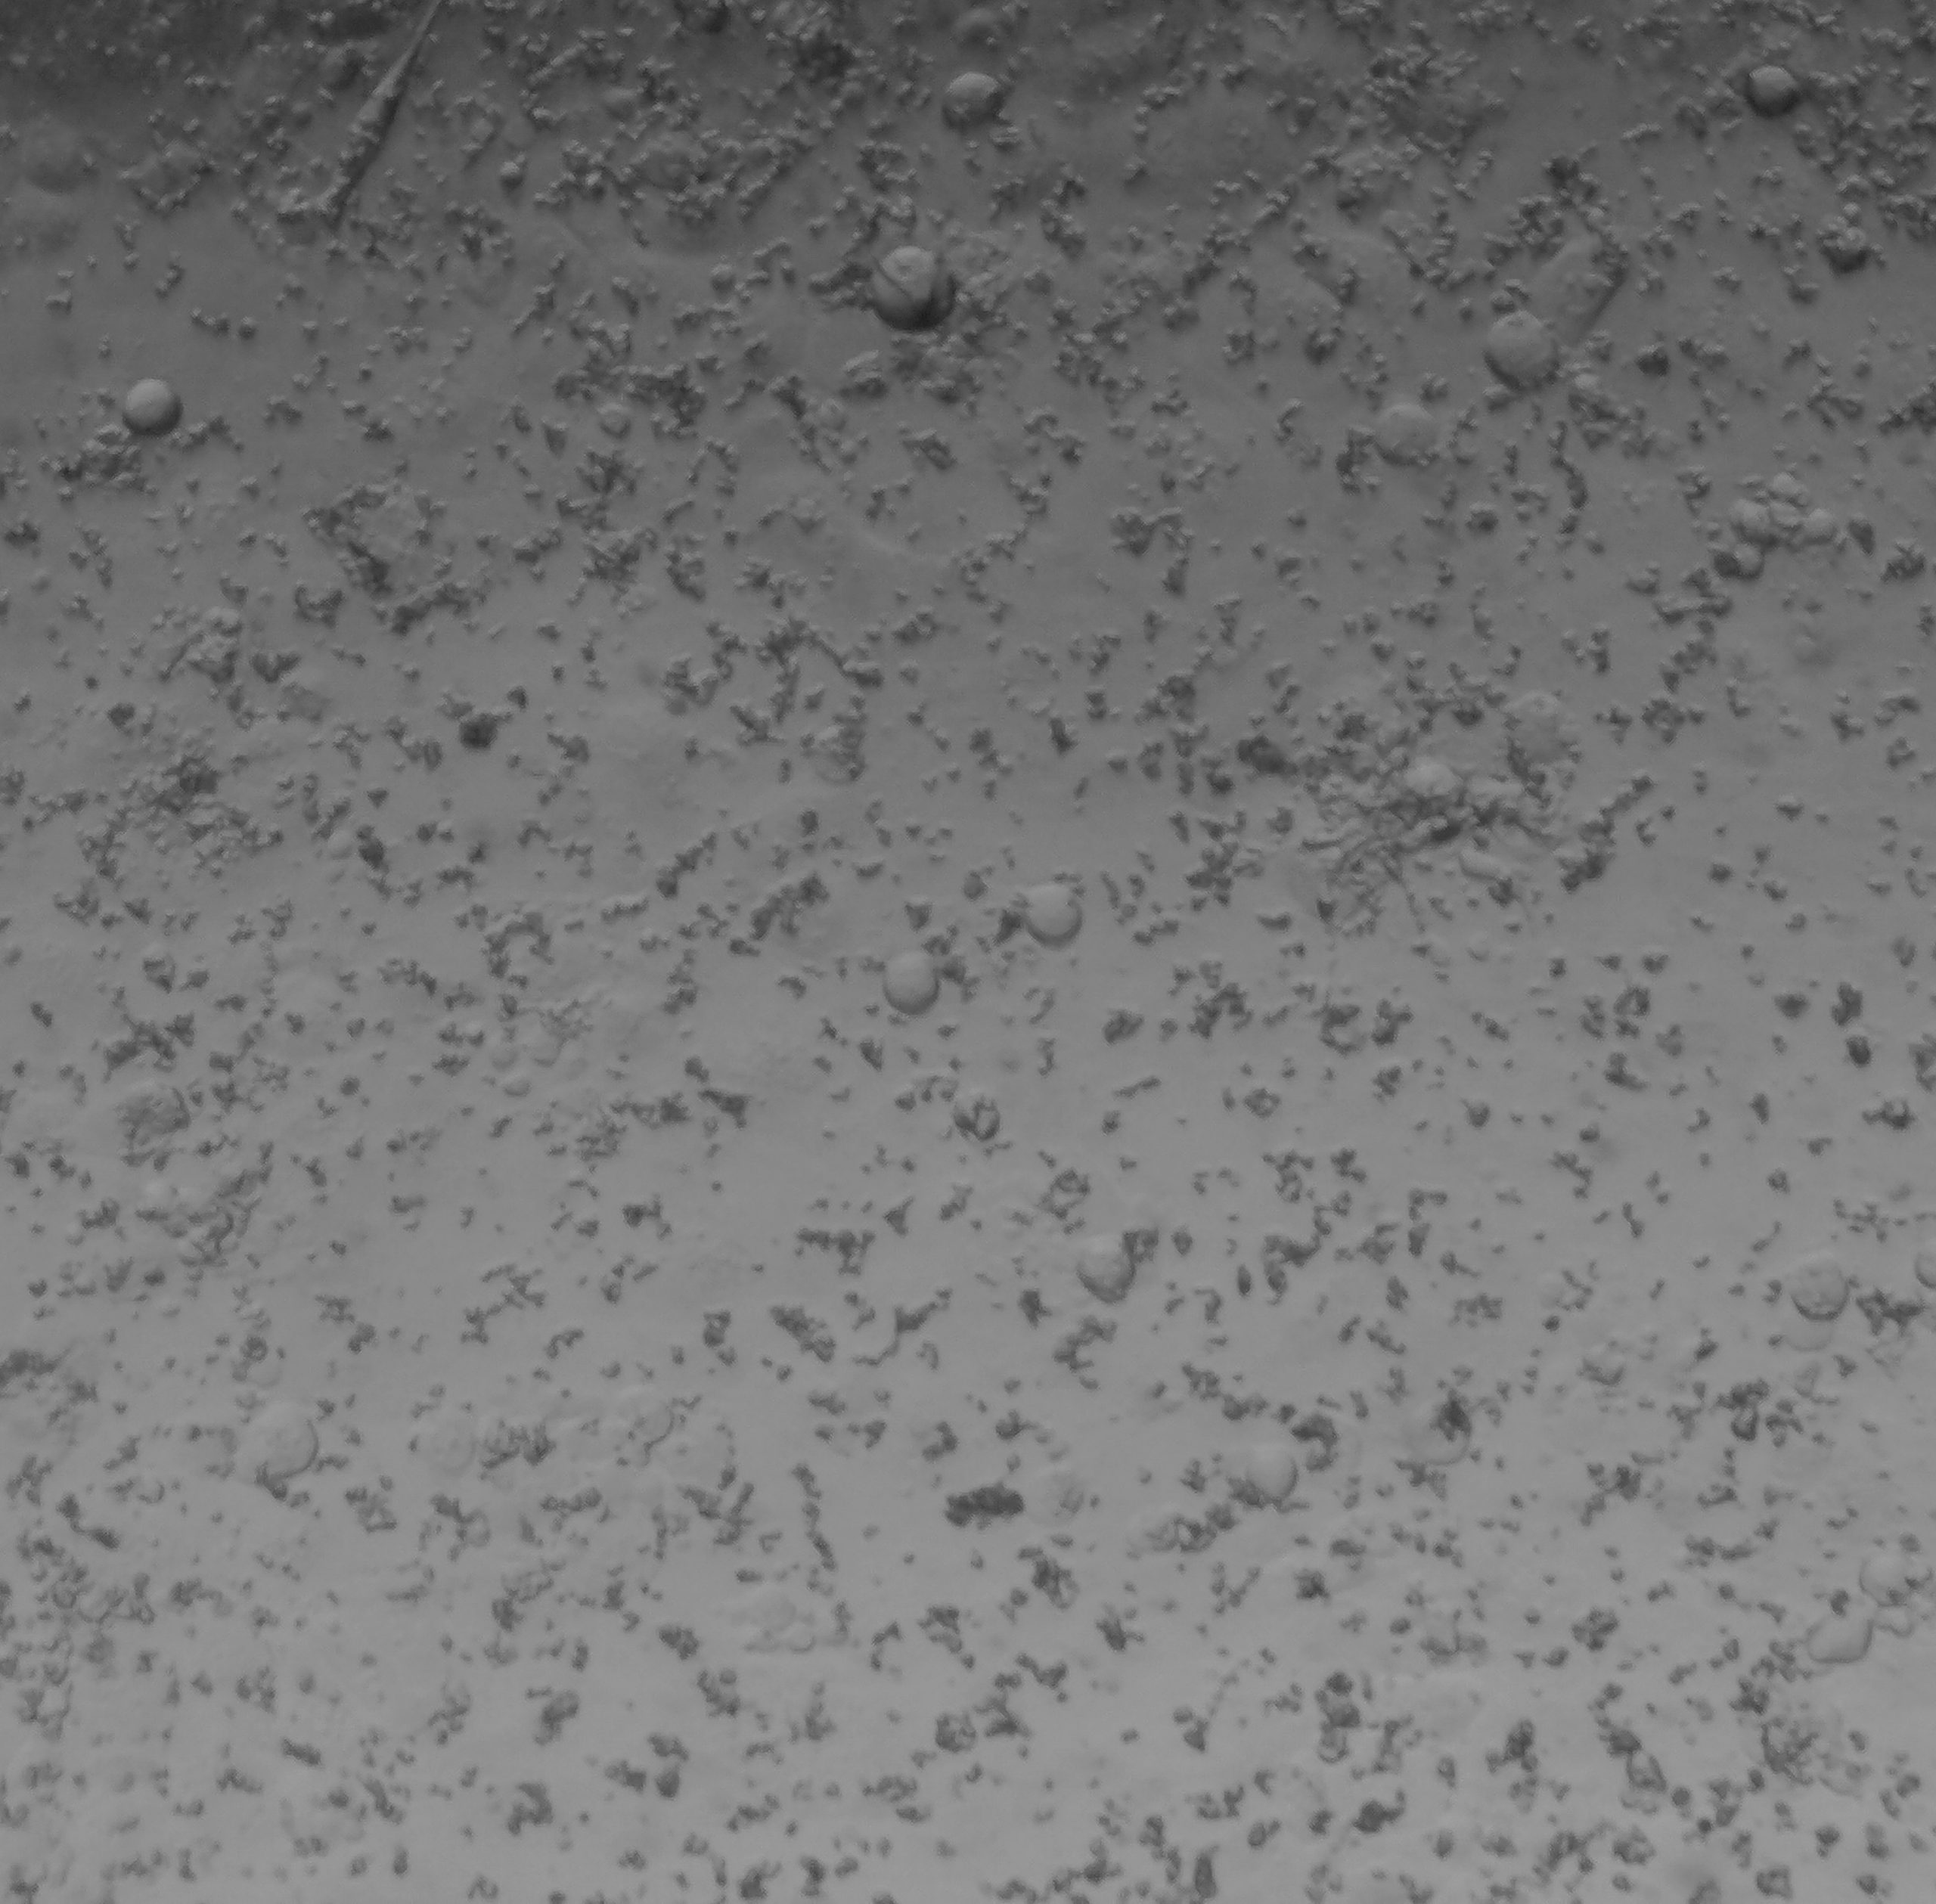

The images below offer a firsthand glimpse into our progress.

Untreated PMP Cell Culture 441

Untreated PMP Cell Culture 457

Treated PMP 441 Cells

Mitomycin C Dose: 1uM

Treated PMP 457 Cells

TRAABA24 Dose: 0.1uM